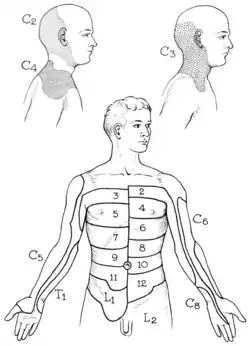

Nerve supply and passage

The skin around the shoulder is supplied by C2-C4 (upper), and C7 and T2 (lower area). The brachial plexus emerges as nerve roots from the cervical vertebrae C5-T1. Branches of the plexus, in particular from C5-C6, supply the majority of the muscles of the shoulder.[3]